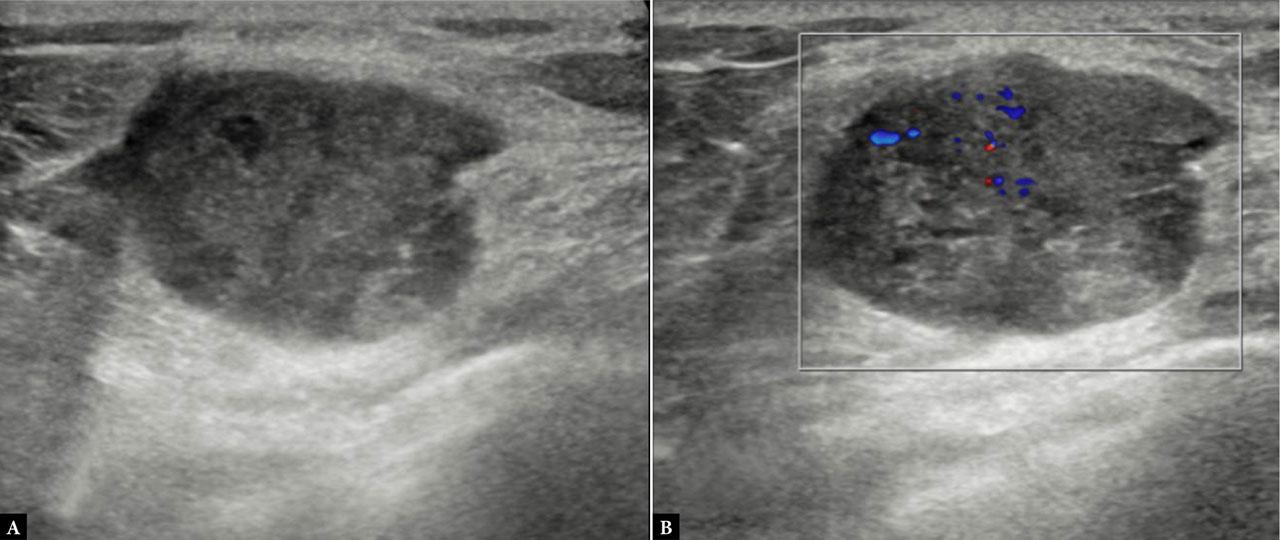

Fig. 4.